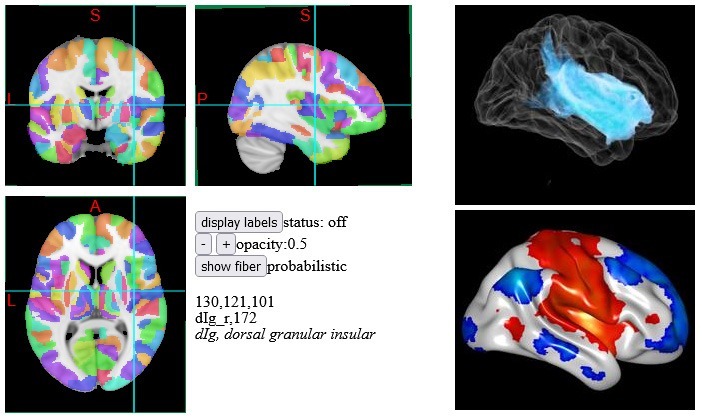

Then, we mapped the connectivity to the lesion in the left insula, as shown in Figure 3. Intriguingly, mapping the connectivity from left insula lesion showed a much smaller region of affected brain tissue compared to the effect of the thalamic lesion. Thus, the smaller thalamic lesion on the CT brain scan actually connects to a much larger region of brain than the bigger lesion in the insula does. So, connectomics allows us to visualise information that is not apparent from the standard CT brain scan. Functionally, the thalamic lesion is more consequential, even though the visible extent is smaller on the CT brain scan.

This is an significant finding and brings out the importance of connectomics. It allows us to better understand the effects of a brain injury. Typically, this is not something on the radar of a claims assessor. Let’s change that!